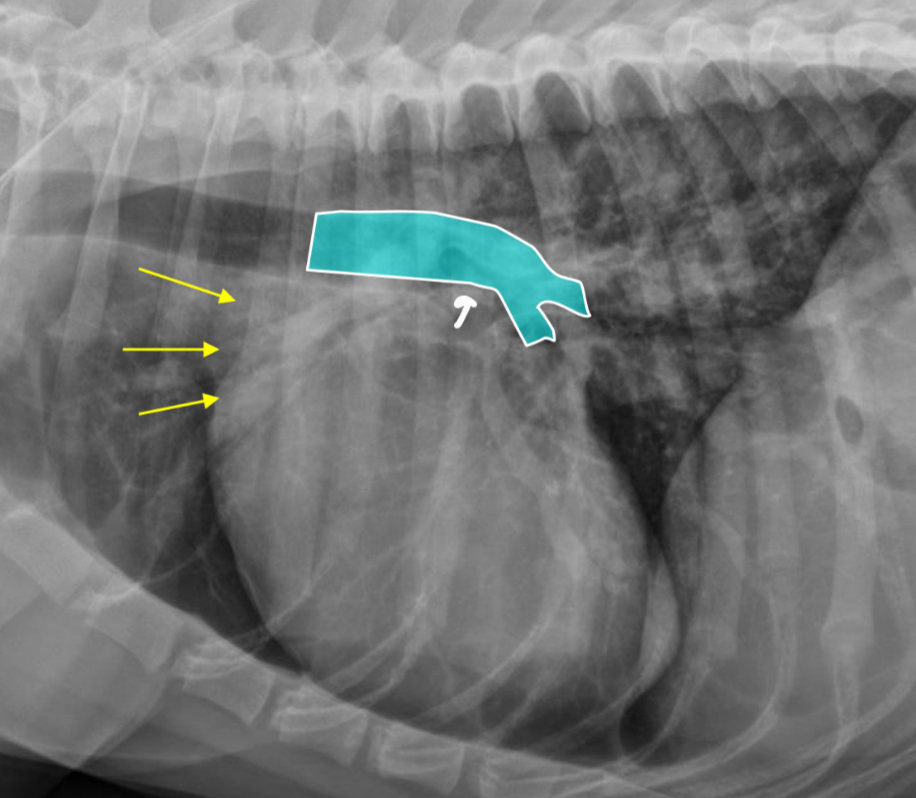

What part of the heart is enlarged

LAE

3 features of LAE on DV

-double opacity sign

-separation of main stem bronchi

-LA bulge at 2:30-3 o’clock